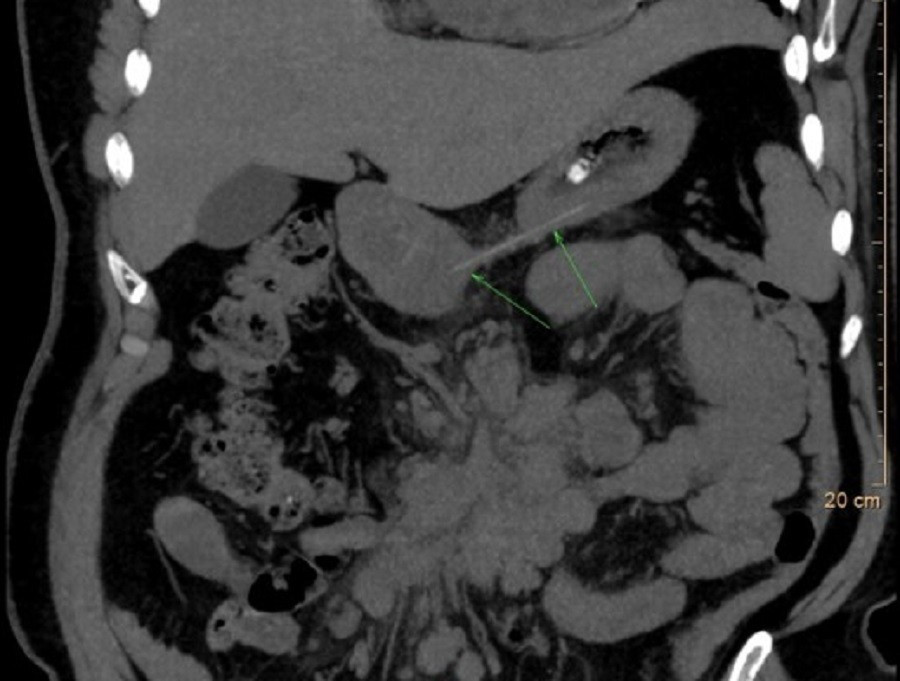

Dị vật đường tiêu hóa là tình huống thường gặp nhưng đặc biệt nguy hiểm nếu không được can thiệp sớm

Khi đến bệnh viện, người bệnh trong tình trạng đau họng dữ dội, nuốt rất khó và bắt đầu xuất hiện khó thở. Nội soi thanh quản cho thấy sụn thanh thiệt và sụn phễu phù nề nghiêm trọng, mất rãnh lưỡi – thanh thiệt, che lấp gần như toàn bộ đường thở. Chụp CT xác định tình trạng phù nề nặng ở thanh thiệt, sụn phễu và đáy lưỡi, nguy cơ tắc nghẽn đường thở rất cao, có thể đe dọa tính mạng nếu không xử trí kịp thời.